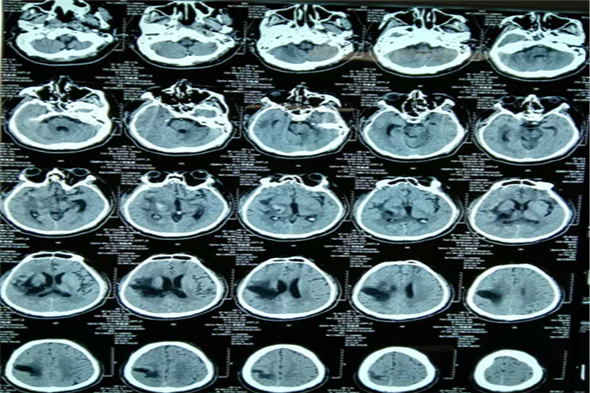

病例三 王某,男,66岁,脑出血、脑疝。

术前脑CT片

术后第三天脑CT

术后一周脑CT